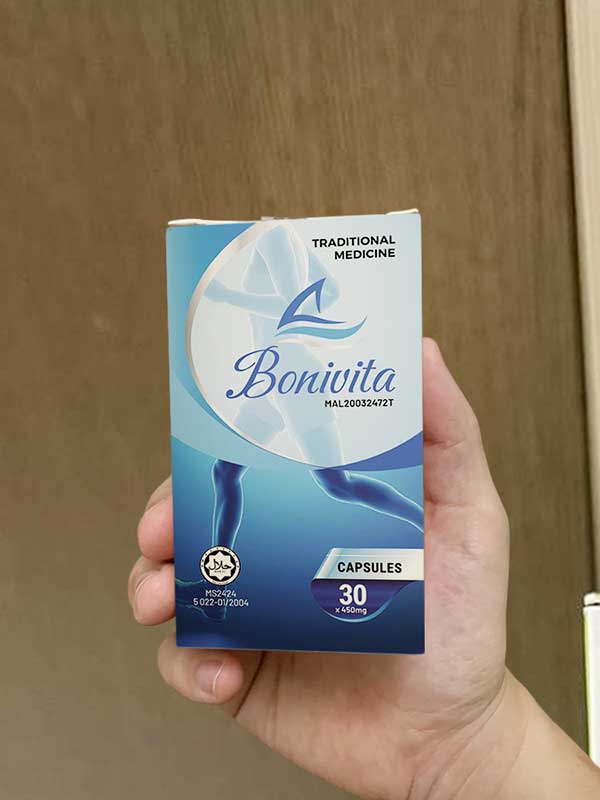

Selepas mencari untuk masa yang lama, saya akhirnya membaca artikel di forum kesihatan di mana seseorang berkongsi bagaimana mereka telah sembuh sepenuhnya dari sakit tulang dan sendi dan masalah lutut. Tidak perlu pembedahan atau suntikan, hanya menggunakan kapsul. Dia berkata hasilnya sangat cepat, dipanggil Bonivita.

Melihat bahawa bahan-bahannya semuanya herba semula jadi, dan harganya berpatutan, dan lagipun, saya sudah membelanjakan begitu banyak wang untuk ubat-ubatan... Saya memutuskan untuk cuba memesannya.

Bukan itu sahaja, produk Bonivita palsu dan tiruan mula muncul di pasaran. Ramai orang yang membeli "kapsul palsu" murah dari sumber yang meragukan mendapati ia tidak berkesan langsung, atau malah mempunyai kesan buruk. Oleh itu, saya hanya mengesyorkan membeli dari laman web rasmi pengeluar, dengan kod pengesahan dan kakitangan menghubungi untuk pengesahan - membeli secara rawak sangat berisiko!

Sejujurnya, saya tidak mengharapkan keajaiban, hanya ingin menguruskan dan menangguhkan pembedahan. Mengejutkan, sejurus selepas mengambil kapsul Bonivita yang pertama, sakit lutut kronik saya tiba-tiba reda, dan keesokan paginya saya boleh berdiri sendiri tanpa sebarang ubat penahan sakit. Pada ketika itu, saya fikir "ini mungkin jalan keluar saya."

Saya membaca arahan dengan teliti dan mengambilnya secara teratur dua kali sehari. Melihat bahawa bahan-bahannya sepenuhnya semula jadi dan mengandungi peptida kolagen memberikan saya ketenangan fikiran.

Yang saya gunakan adalah Bonivita — kapsul yang menyokong kesihatan tulang dan sendi.

Bonivita benar-benar satu kejayaan besar. Keberkesanan Bonivita telah diuji secara klinikal, dipatenkan, berdasarkan penyelidikan bertahun-tahun. Formula terobosan ini membantu memulihkan cecair sendi, menyokong fungsi sendi, dan mengurangkan kesakitan semasa pergerakan.

Produk mengandungi bahan-bahan semula jadi yang bekerjasama untuk membantu sendi berfungsi dengan lebih baik, sambil menambah peptida kolagen dan L-glutathione untuk mempercepatkan proses pemulihan. Kami memutuskan untuk mengeluarkan dan mengedarkan Bonivita di Malaysia.

Walau bagaimanapun, kami menghadapi beberapa halangan. Syarikat farmaseutikal "besar" tidak mahu Bonivita tersebar luas, kerana jika pesakit menggunakan ubat sendi jangka panjang yang lebih sedikit, keuntungan mereka berkurangan. Terutamanya produk yang berharga berpatutan yang memberikan hasil yang mampan. Mereka takut Bonivita akan mengecilkan pasaran ubat penahan sakit jangka pendek. Oleh itu, anda tidak akan menemui Bonivita di farmasi atau pasar raya. Kami hanya mengedarkan dalam talian, pelanggan yang ingin membeli hanya perlu meninggalkan permintaan di laman web rasmi pengeluar.

Nasihat terakhir: Berhati-hati dengan produk palsu dan tiruan yang membanjiri pasaran. Adalah lebih baik untuk membeli dari alamat yang betul untuk mengelakkan "kehilangan wang dan mendapat penyakit." Semoga semua sihat. Jumpa lagi!